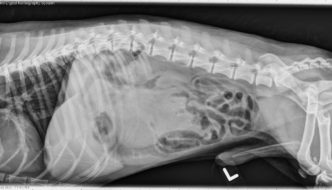

12 year old Labrador-Border Collie cross

Happy new year! Today's case is a 12-year-old female spayed Labrador-Border Collie cross presented to Emergency Services after becoming recumbent and having difficulty breathing this evening. What are your findings? … [Read more...]